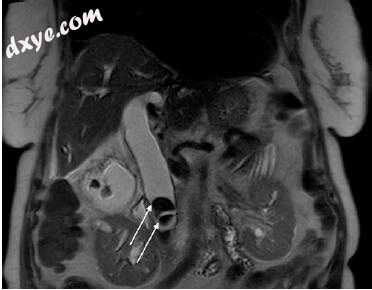

图5.1在冠状动脉T2加权屏气MR序列上看到70岁男性肝胆管结石患者(箭头)在肝胰管的胰后部分。注意蝶翠诗在慢性发炎胆囊中的扩张和进一步的凝固